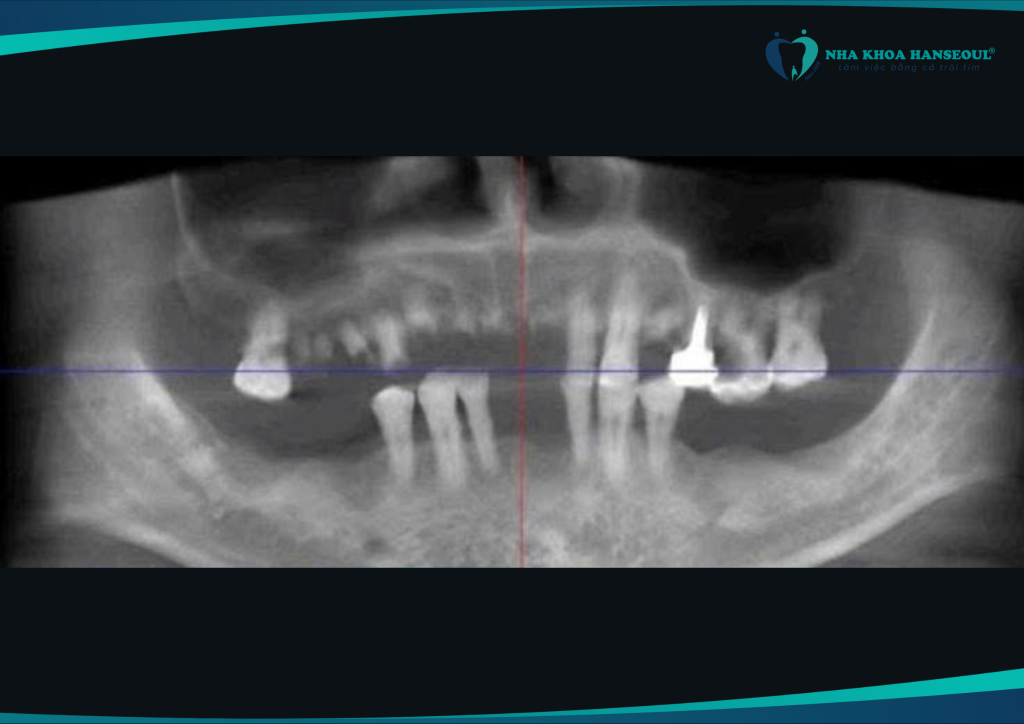

Trước khi tìm đến Nha khoa Hanseoul, chú Lưu Giai Cường (1964) gặp phải tình trạng mất răng gần như toàn bộ hai hàm. Các chân răng còn lại đã bị tiêu xương nghiêm trọng, lộ chân và lung lay mạnh. Ảnh hưởng lớn đến khả năng ăn nhai và chất lượng cuộc sống.

Tại Hanseoul, chú Cường được bác sĩ Phùng Lê Tuấn Anh – chuyên gia phục hình răng Implant nhiều năm kinh nghiệm – trực tiếp tư vấn và xây dựng phác đồ điều trị All On 4 phù hợp, đảm bảo:

- Nhổ bỏ toàn bộ răng lung lay còn lại

2. Cấy 4 trụ Implant All On 4 dòng Osstem TSIII SA

3. Ghép xương sinh học bằng vật liệu SureOss + A-Oss

4. Đặt màng sinh học, khâu kín và cố định trụ Implant

5. Lắp răng sứ Katana cao cấp – mang lại hàm răng tự nhiên, bền đẹp

- Chụp phim CT ConeBeam 3D

- Đo mật độ xương hàm, đánh giá khả năng tích hợp trụ

Nhờ vào kết quả chi tiết này, bác sĩ có thể lập kế hoạch điều trị cá nhân hóa, đồng thời dự phòng biến chứng trong và sau phẫu thuật.